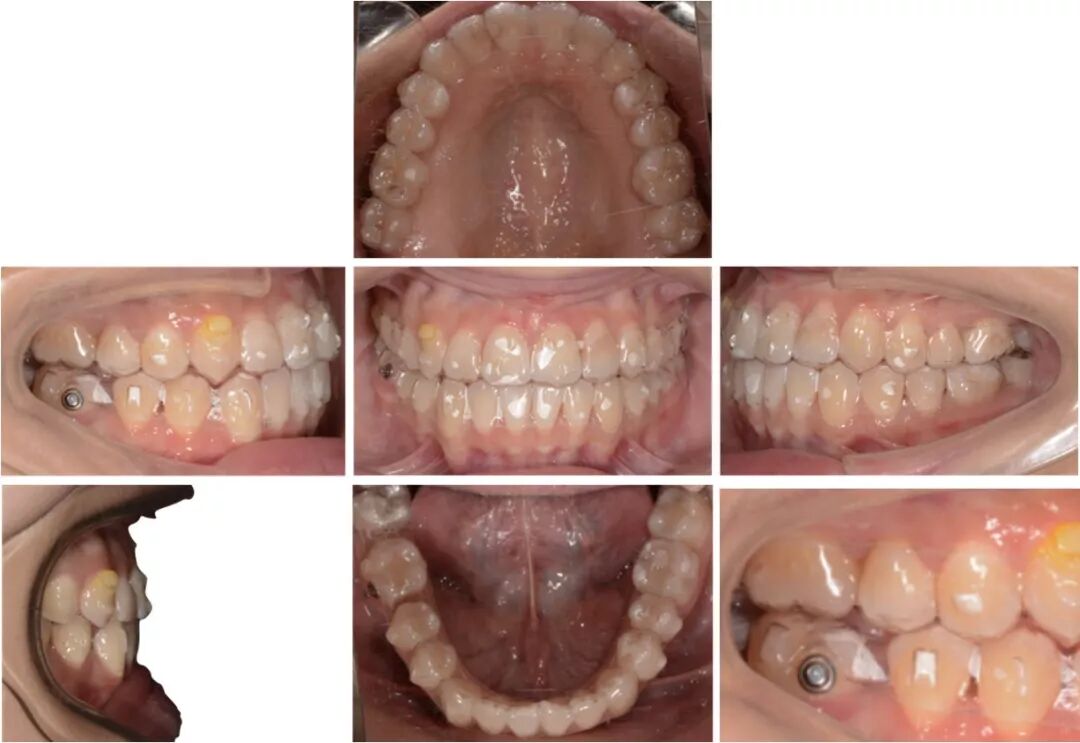

矫治中

第8副,矫治器与牙面贴合,矫治过程中配合III类牵引,有利于尖牙、磨牙关系的改善。

第20副,矫治器与牙面贴合,近中矩形附件使矫治器对47牙有较好的固位,47牙与45相对移动,磨牙尖牙关系改善。

第30副矫治器时,其余牙位矫治器还是比较贴合,但是47牙近中出现了低合与矫治器间隙变大,嘱患者使用咬胶,利用矫治器的力量竖直47牙。

第33副,由于47牙持续的前倾,我们进行了矫治设计的反馈,患者由于干扰的去除,咬合支点的前移,出现了颌位的后退。因为这个原因,实现了比矫治设计更好的尖牙磨牙关系。所以这次我们反馈时提交的是cr位的咬合记录。

矫治中 反馈:

47牙前移的矫治设计:竖直并后倾磨牙6°,每步移动0.16 mm,磨牙前移时维持每步0.5°后倾,与对合设计咬合重接触。

反馈的矫治方案,上颌内收前牙关闭剩余散隙,下颌竖直前移磨牙,关闭间隙。

第5副,II类牵引来辅助47牙前移,给它部分垂直向分力,但由于水平向上分力更大,使其更前倾,我们停止了长牵引的佩戴。

第30副,改为局部牵引,根据牙齿移动的情况设计牵引,给予其更多的垂直向分力。

第34副矫治器时,48牙近远中和垂直向移动的情况不是太好,我们使用了一个三角形牵引,以矫治器作为引导,帮助它向近中合方移动。

反馈后37副矫治器后,我们完成了矫治,总疗程共30个月。在成功的磨牙长距离前移中,未辅助固定矫治。